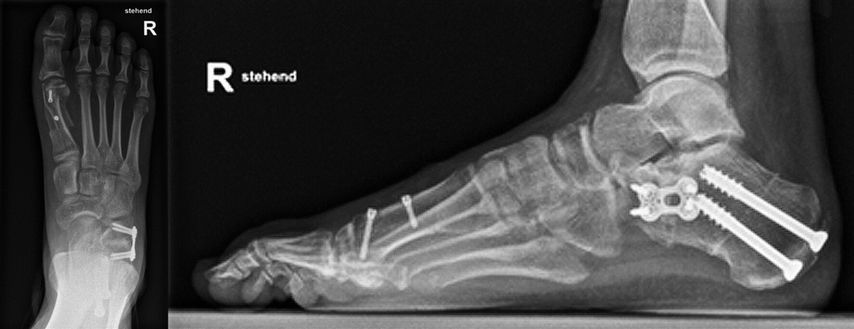

Bei der Erkrankung im Stadium II haben die Patienten eine flexible Plattfußdeformität mit Insuffizienz der Tibialis-posterior-Sehne, abgeflachtem Fußgewölbe, Vorfußabduktion und Rückfußvalgus. Die chirurgische Behandlung beinhaltet in der Regel eine Form der Rekonstruktion der PTT, üblicherweise durch Transfer der Flexor-digitorum-longus(FDL)-Sehne, kombiniert mit einer Fersenbeinosteotomie, entweder einer Verlängerung der lateralen Säule und/oder einer medialen Verschiebeosteotomie des Tuber calcanei (Abb. 3).

Abb. 3: Calcaneusdoppelosteotomie: „lateral lengthening“ und medialisierende Verschiebeosteotomie zur Korrektur der Rückfußachse und Vorfußabduktion (Patient von Abbildung 1)

Ein eventuell bestehender Vorfußvarus (= Vorfußsupination) wird, je nachdem ob die Ursache in einer Instabilität oder in einer Arthrose liegt, mit einer plantarisierenden TMT-Arthrodese (modifizierter Lapidus) oder mit einer dorsalen „Opening wedge“-Osteotomie des Os cuneiforme mediale (= Cotton-Osteotomie) korrigiert.Schließlich wird die Verkürzung des Gastrocnemius-Soleus-Komplexes und der Verlust der Dorsalextension im OSG bei korrigiertem Rückfuß beurteilt und bei Bedarf mit einer Verlängerung der Achillessehne oder der Gastrocnemiusaponeurose korrigiert. Zusätzliche Verfahren, wie die Rekonstruktion des Spring-Ligaments, werden bei Bedarf ebenfalls im gleichen Eingriff durchgeführt.